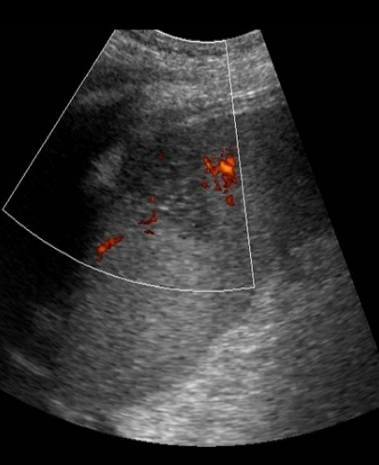

Identify this image.

Splenic infarct

What is the sonographic appearance of splenic infract?

Hypoechoic wedge shaped area

Bring band sign seen as echogenic linear-shaped bands within infarct

Avascularity